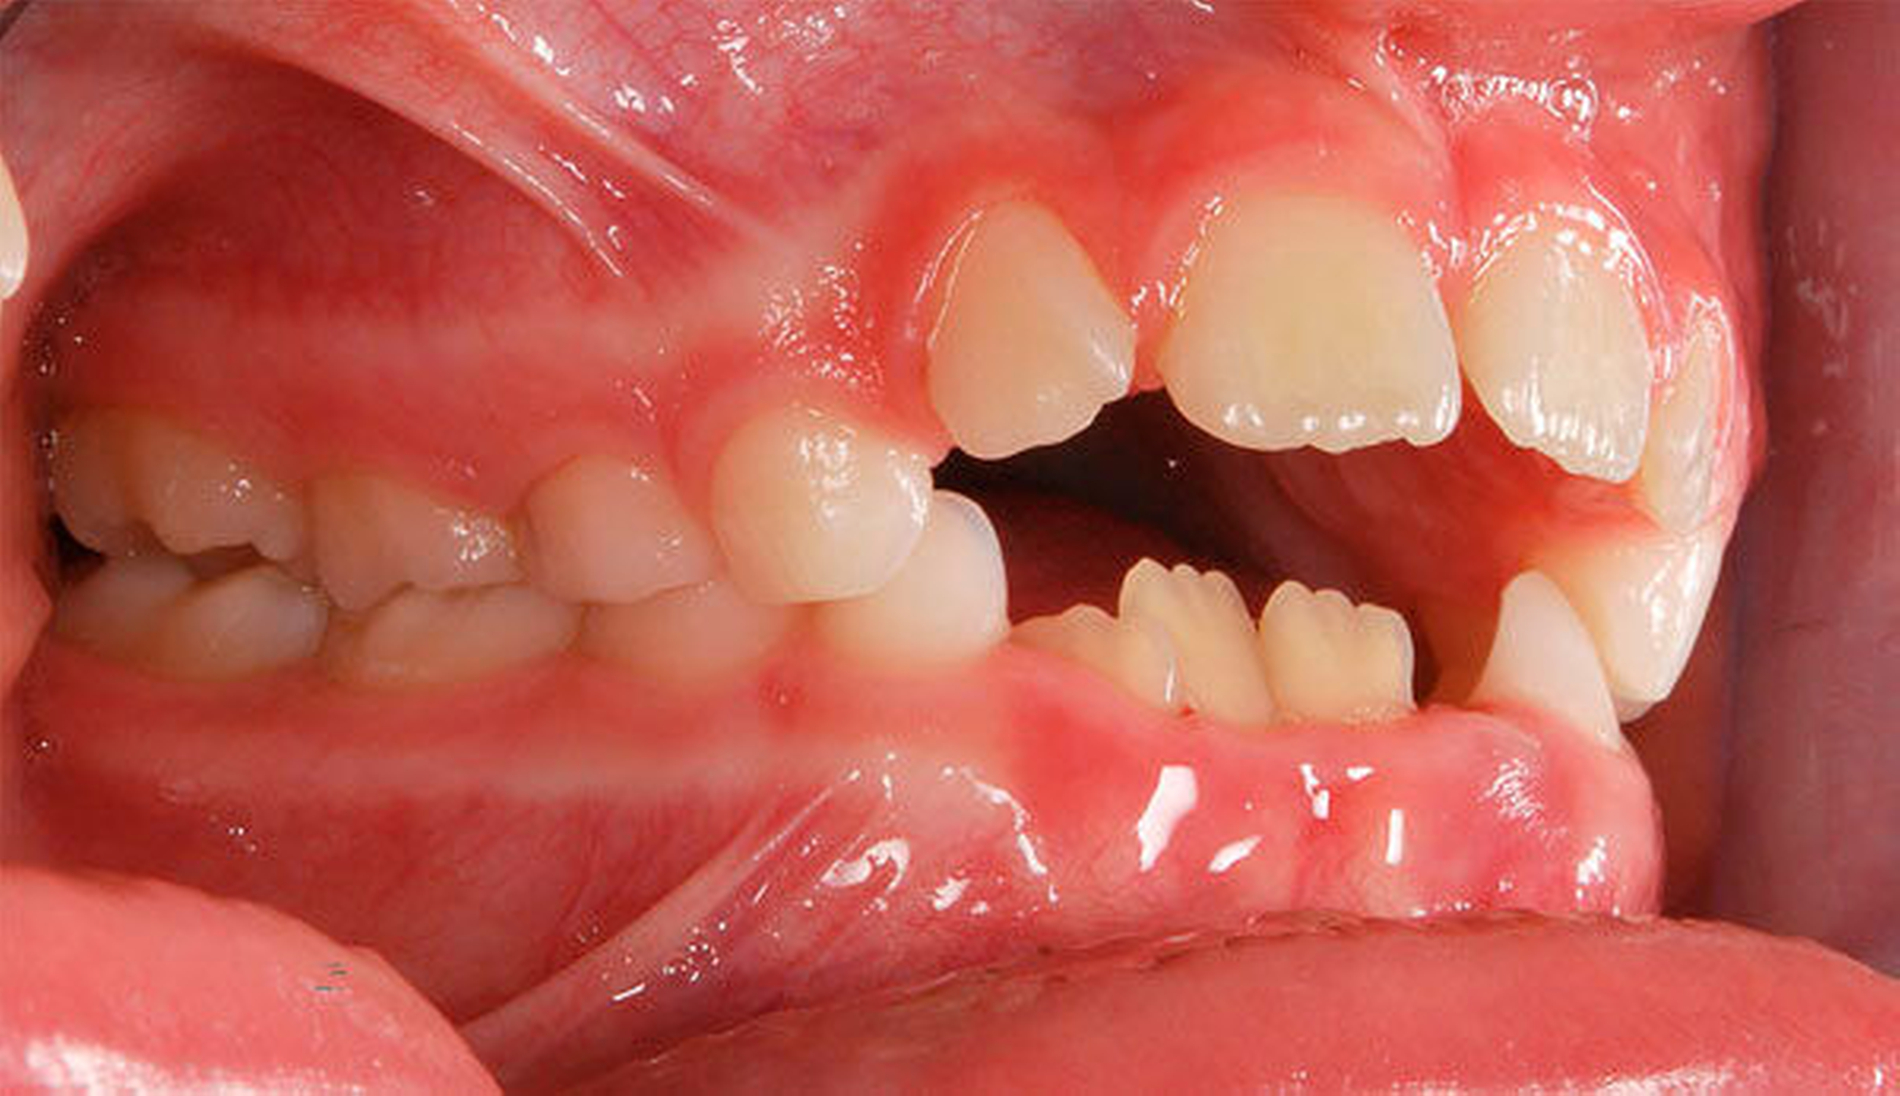

Ausgeprägte Zahnfehlstellungen und Gebissanomalien zeigen sich im reinen Milchgebiss deutlich seltener als im Wechsel- oder im permanenten Gebiss [Schopf, 2003]. Dennoch sollten bereits in dieser frühen Phase beispielsweise die Platzverhältnisse für die später durchbrechenden Zähne beurteilt werden. Im Säuglingskiefer liegen die Zahnkeime der Milch-Inzisiven zunächst in einer sagittalen Staffelstellung [van der Linden, 1980]. Die mit dem Durchbruch der Milchzähne einhergehende Bildung des Alveolarfortsatzes und die wachstumsbedingte Vergrößerung der Zahnbögen führt meist zu einer lückigen Stellung der Milchschneidezähne [Sillman, 1964] (Abbildung 1). Diese Lücken tragen dazu bei, den deutlich breiteren bleibenden Nachfolgern eine regelrechte Einordnung in den Zahnbogen zu ermöglichen [Moyers, 1976; Leighton, 1978]. Ein „schönes“, lückenloses Milchgebiss oder gar Engstände in der Front sind ein Alarmsignal im Hinblick auf spätere Platzprobleme für die bleibenden Zähne [Leighton, 1969]. Bei diesen Patienten ist eine intensive Überwachung während des Zahnwechsels der permanenten Inzisiven ratsam, um gegebenenfalls rechtzeitig Platz schaffende Maßnahmen einleiten zu können.